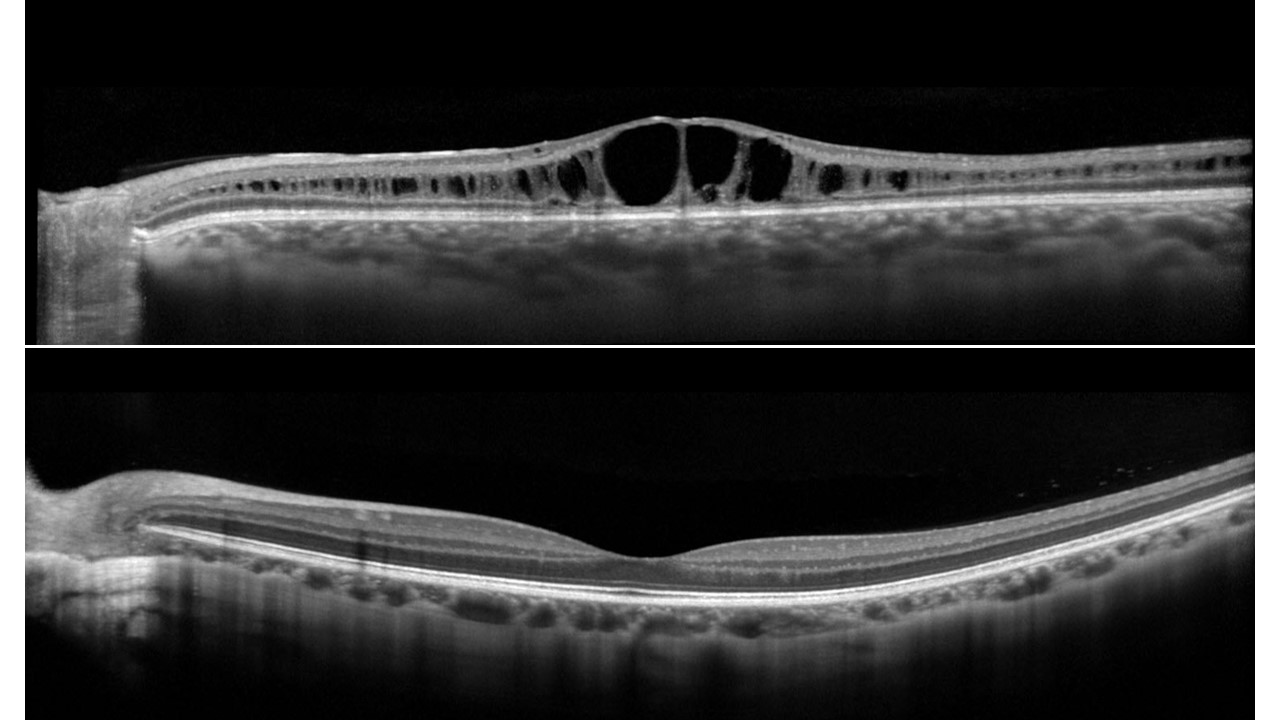

Pioneering Optoretinography in Patients with Retinal Disease

A new imaging technique called OCT optoretinography (ORG) captured an image of photoreceptor dysfunction in a relatively wide area of 6x6 mm in the macula. ORG could provide a precise way to assess the effectiveness of therapies in earlier stages of the disease.